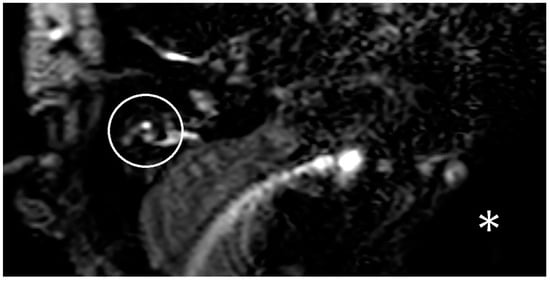

In the following months, there was increasing hearing loss on the right side. Besides the hearing loss, new caloric testing indicated a conspicuous change on the contralateral side too. In the following months, the patient showed further vertigo attacks and new hearing loss on the contralateral ear. An MRI with a hydrops sequence was performed, but no hydrops was demonstrated on the right side (Figure 2).

Figure 2. A visualization of a three-dimensional fluid-attenuated inversion recovery (3D-FLAIR) sequence with delayed contrast of the MRI of patient two. The right inner ear is marked with a white circle. Because of an artifact of the implant, the implanted side cannot be seen. The artifact is labeled with a white star. There is no hydrops on the right side.